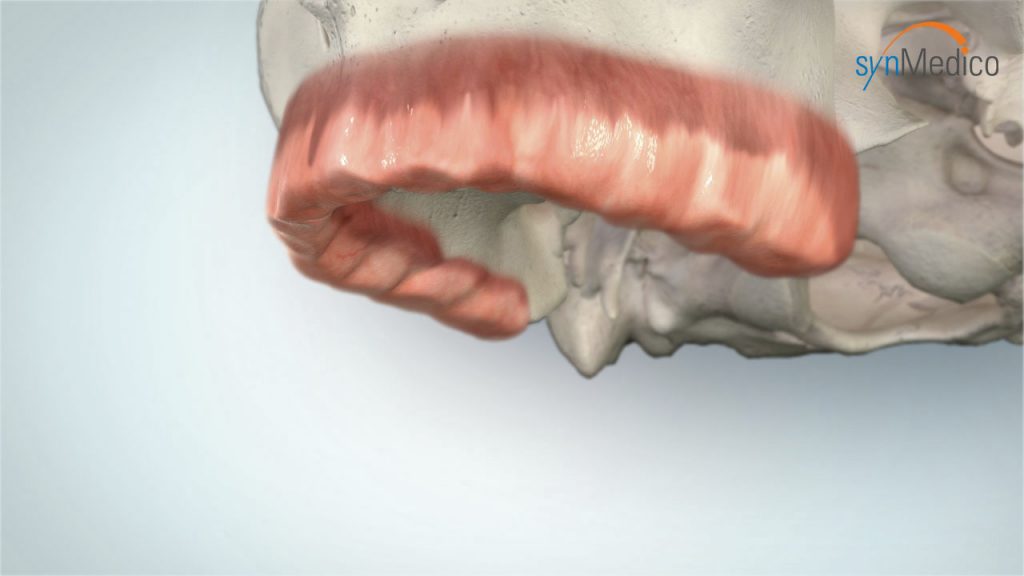

Zahnloser Kiefer

Auch ein zahnloser Kiefer kann mit Implantaten komfortabel versorgt werden. Bereits bestehender Zahnersatz gewinnt auf Implantaten neuen, verbesserten Halt. Das Gesichtsprofil bleibt erhalten, Essen und Lachen ist kein Problem mehr, die Aussprache wird deutlicher. Der Patient kann sich auf einen wirklich funktionierenden Zahnersatz verlassen.